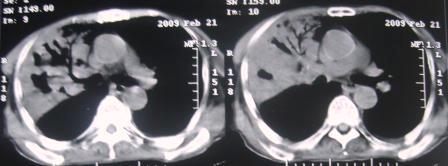

xx 男 63岁 发热 家属描述有时高热 有时低热 抗酸杆菌阴性 于2月21号 胸片及ct

3月10号复查

楼主  :谢谢大家发言  我和大家考虑的一样干酪性肺炎并播散